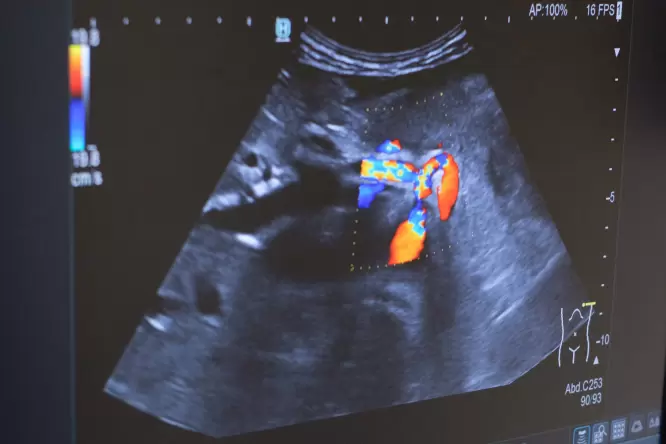

Bei spezieller Fragestellung kann die zusätzliche Farbdoppleruntersuchung Aufschluss über die Durchblutung der Organe geben.